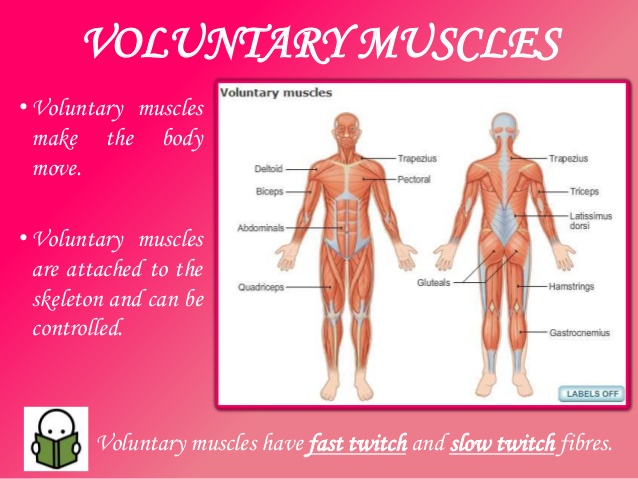

1. Voluntary muscles:

These are muscles under our control. We relax or contract them when we wish to e.g. the pectoral muscles.

1. Voluntary muscles:

These are muscles under our control. We relax or contract them when we wish to e.g. the pectoral muscles.